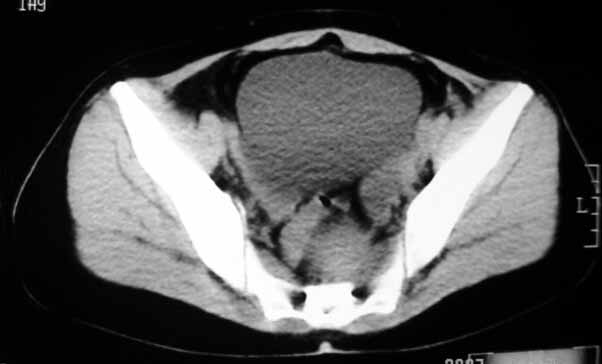

标题: CT8123:女46岁,左下腹胀痛不适1月,以前曾有月经过多史,现已 [打印本页]

标题: CT8123:女46岁,左下腹胀痛不适1月,以前曾有月经过多史,现已

子宫肌瘤,不强化不好说

子宫增大密度较均匀,考虑子宫肌瘤,不强化不好说

考虑子宫肌瘤(变性)或子宫腺肌病,不排除内膜ca可能,不增强建议结合mri或b超检查。

子宫增大密度较均匀,考虑子宫肌瘤可能性大,

建议结合b超